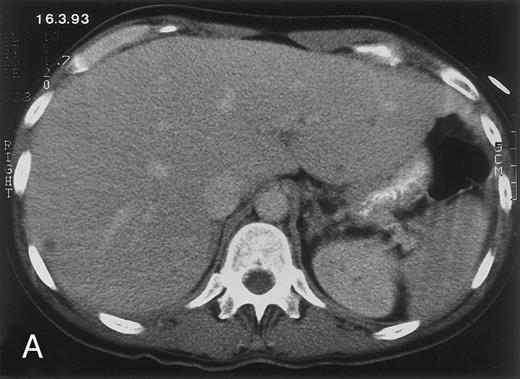

Radiologic evolution in patient A. (A) Postcontrast abdominal CT scan on March 16, 1993 shows multiple small hypodense areas in all segments of the liver, suggestive of hepatic candidiasis. Seven days previously, the patient had recovered from severe neutropenia after the first cycle of chemotherapy for AML. (B) On April 23, 6 days after the neutrophil count had dropped below 500/μL in the second cycle of chemotherapy, there is no evidence of focal lesions on postcontrast CT scan. (C) On June 18, when neutrophils were normalized for 46 days, CT scan again shows multiple small abscesses.

Evolution of fungal lesions on CT scans during and after neutropenia is summarized in Table 2. Figure 1 (patient A) and Fig 2 (patient B) serve to illustrate Table 2.

In three patients, multiple round lesions were seen on postcontrast CT scans of the abdomen in the liver and the spleen, while in two cases, lesions could only be seen in the liver (Table 2). Following the diagnosis of disseminated candidiasis, these lesions decreased in size and visibility during subsequent neutropenia in three patients (compare Fig 2A and B) and disappeared completely in two patients (compare Fig 1A and B). The numbers of days of severe neutropenia (neutrophils <500/μL) at the time the CT scan was performed are listed in Table 2. After recovery from neutropenia and despite continued antifungal therapy, the size and visibility of the lesions increased again (Fig 1C). Similarly, the number of days since recovery from severe neutropenia (neutrophils >500/μL) are listed in Table 2. In two of three patients treated with another cycle of myeloablative chemotherapy, this waxing and waning pattern of radiologic lesions could be seen again (Fig 1D and E). In all patients, lesions eventually disappeared (Figs 1F and 2D) after prolonged antifungal therapy.

Diagnosis of disseminated candidiasis is often difficult, because cytologic, histologic, and microbiologic findings may remain negative.1 3 Biopsy confirmation of diagnosis was achieved in four of five cases. The initiation of antifungal treatment before biopsy in patient A may have contributed to the negative pathologic findings. Nevertheless, the typical presentation with right upper abdominal discomfort, persistent fever after resolution of prolonged neutropenia, elevated C-reactive protein level, and typical multiple lesions on CT scan (Fig 1A), as well as the disease course with eventual total disappearance of lesions under antifungal treatment, was sufficient evidence to establish the diagnosis in patient A.